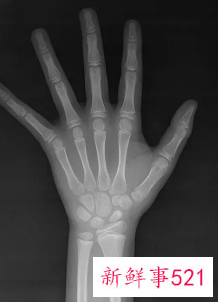

比较简单的方法就是去拍一个X光,借助于骨骼在X光摄像中的特定图像来确定。通常要拍摄人左手手腕部的X光片,医生通过X光片观察左手掌指骨、腕骨及桡尺骨下端的骨化中心的发育程度,来解读确定骨龄。

骨龄鉴定是指人的生长发育可用两个“年龄”来表示,即生活年龄(日历年龄)和生物年龄(骨龄)。骨龄是骨骼年龄的简称,借助于骨骼在X光摄像中的特定图像来确定。在了解人的骨龄情况时,通常要拍摄人左手手腕部的X光片,医生通过X光片观察左手掌指骨、腕骨及桡尺骨下端的骨化中心的发育程度,来确定骨龄。